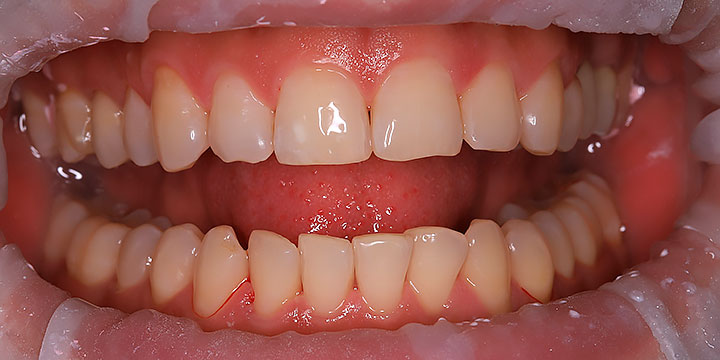

Ходили с мужем на гигиеническую чистку к доктору Алексею. Расположил с первой секунды, заботливо проговаривал каждое свое действие, включил фильм, сделал фото до/после. Процедура сама по себе не из приятных, но конкретно эта оставила только приятные впечатления????